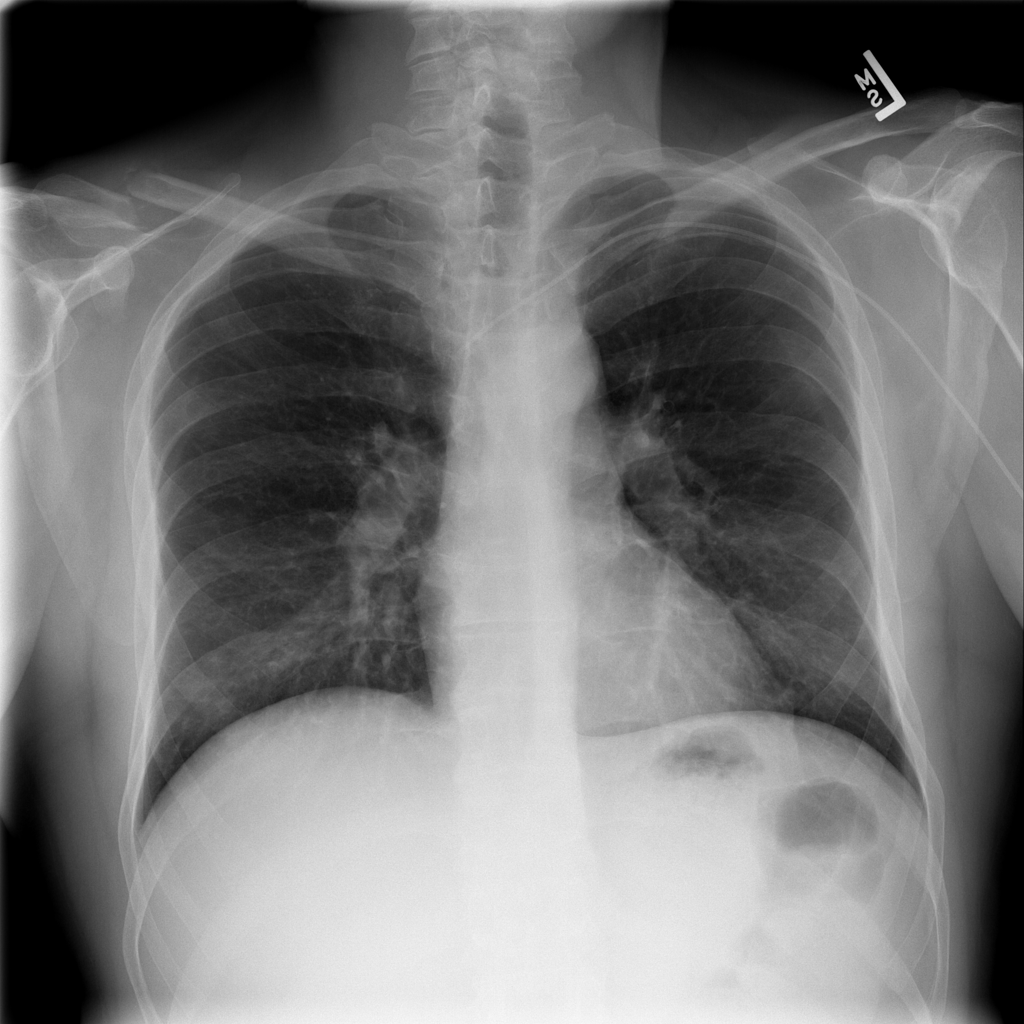

Mass

A mass is a larger focal opacity or lesion seen on the image. It is a descriptive finding that can have several causes and usually needs more imaging or clinical context to characterize.

PAT-4639 · IMG-024Mass

PAT-4639 · IMG-024

AP